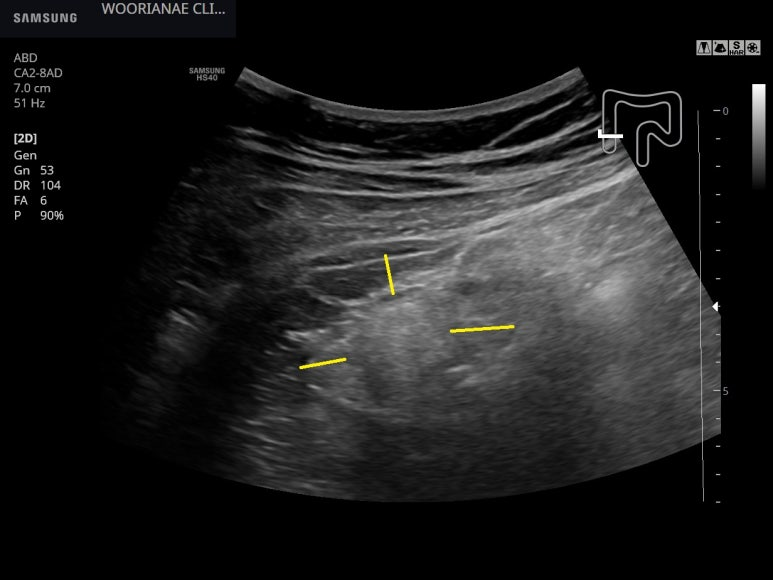

우선 맹장/상행결장의 관찰; 후방감쇄가 뚜렷하지 않으나, 염증성 지방변화도 쉽게 관찰되지 않는데...

컨벡스로 조망하면 화살표쪽에 염증성 지방변화가 있어 보이나, 위에 사진으로 판단하고 보면 그렇게 보일 정도이다.

image 18부터 복벽에 닿아 있는 cecum/proximal A를 확인함